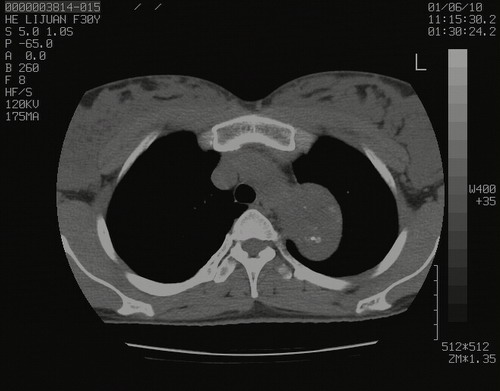

怀孕3个月时(2009-3至4月间),自述突感左侧前后胸疼痛1天,以前胸明显,随后偶感闷痛,余未见异

左肺尖脊柱旁沟肿块,境界清楚,边缘光滑,密度不均,内有多发点片状钙化,考虑良性肿瘤,骨软骨瘤或神经源性肿瘤可能,肺错构瘤不除外。

左后上纵隔见一类圆形肿块影,外侧边界清,密度不均匀,内可见点状钙化影,增强呈不均匀强化,考虑神经源性肿瘤可能。期待病理结果。